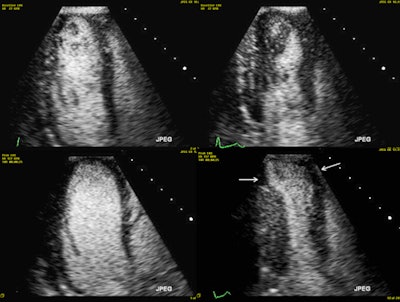

Exercise stress echocardiography with ultrasound contrast agent. Top row: Rest images in diastole (left) and systole (right; there is some contrast swirling due to lower cardiac output at rest). Bottom row: Peak stress images in diastole (left; note the dilatation of the left ventricle) and systole (right; note that the apical segments become severely hypokinetic -- white arrows). All images courtesy of Dr. Alexandros Papachristidis.Conflicting advice

Invasive coronary angiography of the same patient. The black arrow shows a very tight narrowing in the proximal left anterior descending artery.They used the Bruce treadmill exercise protocol for the exercise stress echo, aiming to reach the maximum predicted heart rate. Standard images were acquired at rest and immediately after peak exercise. For the dobutamine stress echo, they used the standard 3 min stages protocol with incremental dobutamine doses of 5, 10, 20, 30 and 40 µg/kg/min. Ultrasound contrast was administered if at least two myocardial segments weren't seen on baseline echo images.